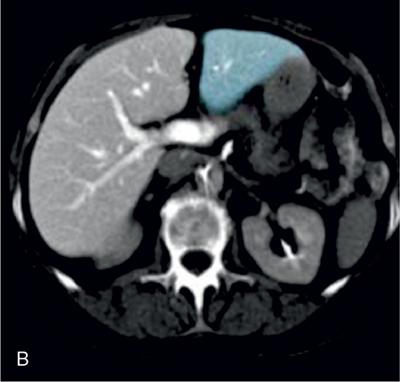

Ritu K. Kashikar, Shrinivas B. Desai Imaging is the mainstay of noninvasive diagnosis of the spectrum of abdominal pathologies or proving absence off thereof. Knowledge of normal anatomy and important normal variants is thus essential for the radiologist in order to avoid misinterpretation or erroneous diagnosis. This chapter highlights the normal anatomy of the hepatobiliary systems including the blood vessel and draining ducts and discusses relevant anatomical variants which may have important clinic implications. The liver is the largest abdominal organ, occupying the right upper abdominal quadrant and is in close approximation with the diaphragm, stomach and the gallbladder. It is largely covered by the costal cartilages. The liver is encapsulated by Glisson’s capsule which is a dense layer of connective tissue. It is covered by peritoneum, except in the regions of gallbladder fossa, fossa for inferior vena cava (IVC), and the bare area. The bare area is the posterocranial aspect of the liver, adjacent to the dorsal body wall, which is not covered by peritoneum. The liver has two surfaces, the convex diaphragmatic surface and a concave visceral surface. The slit in the hepatic hilum is called the porta hepatis and is penetrated by the right and left hepatic ducts (LHDs), hepatic artery and portal vein (PV). The distal portion of the lesser omentum is called the hepatoduodenal ligament and contains the common bile duct (CBD), hepatic artery, PV, nerves of liver and lymphatics. The liver has dual blood supply with hepatic artery providing 25% of hepatic blood and rest by portal vein (Fig. 9.2.1). Five ligaments connect the liver to the undersurface of the diaphragm. These include the falciform, the coronary and two lateral ligaments, all of which are peritoneal folds. The fifth ligament is a fibrous cord-like structure and represents the obliterated umbilical vein. The peritoneum invaginates into the liver parenchyma leading to formation of fissures. There are four normal fissures: fissures for the ligamentum teres, ligamentum venosum and gallbladder and the transverse fissure (Fig. 9.2.2). The liver is organized into microscopic functional units called lobules or acini. A central terminal hepatic venule surrounded by four to six terminal portal triads form a polygonal unit called the hepatic lobule. The terminal portal triad branches line the periphery of the unit. Between the terminal portal triads and the central hepatic venule the hepatocytes are arranged in one cell thick plates, surrounded by sinusoids. The blood flows from the terminal portal triad through sinusoids into terminal hepatic venule. Bile formed within the hepatocytes empties into terminal canaliculi which coalesce into the bile ducts (Fig. 9.2.3). This structure of the functional hepatic unit forms the basis of various functions of the liver. The normal relations of the liver are: The liver can be divided into right, left and caudate lobes. The right and left lobes are separated by the interlobular fissure and is oriented along a line passing through the gallbladder fossa inferiorly and the middle hepatic vein (MHV) superiorly (Fig. 9.2.4). This plane runs from the left of the IVC to the left of the gallbladder fossa and is a called the Cantlie’s line. Use of standardized, segmental anatomy is imperative because it facilitates communication and treatment planning. The segmental anatomy of liver is primarily based on vascular anatomy. The right lobe is divided into anterior and posterior sectors by of the right hepatic vein (RHV). The left lobe is divided into medial and lateraI sectors by an oblique plane connecting the left hepatic vein (LHV) and the falciform ligament. The liver is divided into upper and lower segments at the level of main portal vein (MPV) bifurcation (Fig. 9.2.5). Various systems are used in classification of liver anatomy. These are discussed in Table 9.2.1. The Couinaud’s system is the most commonly used and divides eight sections/segments which are discussed in details below (Table 9.2.2). 1. Segment 1 – Caudate lobe Bounded anteriorly and medially by the fissure for ligamentum venosum (Fig. 9.2.6). 2. Segment 2: Superior segment of the left lateral sector/section Bounded medially by falciform ligament and inferiorly by plane of MPV, also known as the posterior lateral sector (Bismuth, FCAT) (Fig. 9.2.7). 3. Segment 3: Inferior segment of left lateral sector/section Bounded medially by the falciform ligament and superiorly by the plane of the MPV bifurcation, also referred to as lateral anterior sector (Bismuth, FCAT) (Fig. 9.2.8). 4. Segment 4: Left medial sector/section Bounded laterally by falciform ligament and medially by Cantlie’s line (Fig. 9.2.9). 5. Segment 5: Inferior segment of the right anterior sector/section Bounded anteriorly by the gallbladder fossa and posteriorly by the plane of the RHV, superiorly bounded by the plane of MPV bifurcation (Fig. 9.2.10). 6. Segment 6: Inferior segment of the right posterior sector/section Bounded anteriorly by plane of the RHP and superiorly by the plane of the MPV bifurcation (Fig. 9.2.11). 7. Segment 7: Superior segment of the right posterior sector/section Bounded anteriorly by the plane of the RHV and inferiorly by the plane of the MPV bifurcation (Fig. 9.2.12). 8. Segment 8: Superior segment of the right anterior sector/section Bounded anteriorly by the plane of the gallbladder fossa and MHV, posteriorly bounded by the plane of the RHV and inferiorly by the plane of the MPV bifurcation (Fig. 9.2.13). Owing to its broad area of contact with the anterior abdominal wall, the liver is an ideal organ for evaluation with sonography. Ultrasound is commonly used for evaluation of size of the liver. On longitudinal scans obtained through the midhepatic line, if the liver measures 13 cm or less, it is normal in 93% of individuals (Fig. 9.2.14). The size of liver in various planes is discussed in chapter on normograms. When the area of contact between the liver and the anterior border of the right kidney, exceeds below two thirds of the kidney, the liver is considered as enlarged. The normal liver is homogeneous with fine echoes and appears evenly bright. The hepatic veins, PV and fissures interrupt the homogeneity of the liver parenchyma (Fig. 9.2.15). The parenchymal echogenicity may vary depending on the equipment, transducer and gain settings and should be judged by comparison with internal references like right renal cortex, body of the pancreas and PV walls. When compared with the adjacent normal right renal cortex the liver normally appears hyperechoic or isoechoic. The pancreas in a young individual is hypoechoic compared to the liver, and isoechoic in middle aged adults. As age progresses and fatty infiltration of the pancreas occurs, the pancreas appears hyperechoic to the liver. The liver is hypoechoic to the spleen. The normal liver reveals a density of 55–65 HU on nonenhanced scan and should appear homogenous with the exception of hypodensity in the regions of vessels and fissures. The liver parenchymal enhancement is minimal the arterial phase, with increase in density by only approximately 10 HU. This phase is usually to access vascular anatomy and to detect neovascular enhancing lesion like HCC, metastasis. Considering the fact that 75% of heptic venous supply is from the PV, the normal hepatic parenchyma shows maximum enhancement in the portal venous phase. During the venous/delayed phase the hepatic attenuation starts falling (Fig. 9.2.16). The hepatic fissures appear as linear fat containing structures. All the four fissures are well identifies on CT (Figs. 9.2.17–9.2.20). Normal liver should demonstrate uniform T1 signal similar or isointense to the paraspinal muscles and slightly hyper intense to the spleen. No signal drop should be seen on in or opposite phase. On T2W1 images liver appears slightly hyperintense to paraspinal muscles, isointense to pancreas and hypointense to spleen (Fig. 9.2.21). Following administration of extracellular contrast agents the normal liver parenchyma enhances on PV phase similar to that seen on CT. The arterial phase is preserved to determining vascular anatomy, variants and tumoural enhancement. Gadoxetic acid (Eovist) and gadobenate dimeglumine (MultiHance) are hepatobiliary agents showing excretion by the liver. In the case of gadoxetic acid, hepatic excretion is ~50%, which allows imaging in the hepatobiliary phase at ~20 minutes following injection. Gadobenate has only 3%–5% biliary excretion with hepatobiliary phase at approximately 40 minutes (Fig. 9.2.22). This property makes these agents useful in detection of nonhepatocyte containing lesions which appear hypointense to background liver on hepatobiliary phase. Hepatic anatomic variants are relatively common and represent normal interindividual variation of liver morphology. Normal Anatomic Variants Anatomic anomalies Accessory and pseudofissures may be seen in the liver. True accessory fissures result from infolding of the peritoneum usually along the undersurface of the liver and are rare. The inferior accessory fissure is the commonest accessory fissure and divides the posterior segment of the right hepatic lobe into lateral and medial portions. Diaphragmatic slips may cause indentation over the liver surface and are not commonly seen on imaging (Fig. 9.2.23). Leftward extension of the lateral segment of the left hepatic lobe appearing as a crescentic density that wraps around the spleen is referred to as sliver of liver. The left lobe of the liver may exhibit various forms: leaf like; spatular; truncated pyramid/wedge shaped; and a bifid appearance (Fig. 9.2.24). Elongated left lobe may be mimic splenomegaly, perisplenic hypoechoic collections or less commonly tumours. Imaging clues to diagnosis are establishing contiguity with liver and visualization of parenchymal vessels coursing through. The portion of the liver that extends medially from the right lobe between the IVC and fissure for ligamentum venosum is called the caudate lobe. The caudate lobe is divided inferiorly into a lateral caudate process and a medial papillary process. The medial papillary process projects medially towards the pancreatic head and has applied importance (Fig. 9.2.25). Riedel’s lobe is a tongue-like projection from the anterior aspect of the right lobe and the most common accessory lobe of the liver. It is seen most frequently in asthenic women. The reported prevalence of RL, ranges from 3.3% to 14.5% and the prevalence is higher in women than in men. It can be 20 cm or more in length and may extend up to the iliac fossa. It is usually asymptomatic and is discovered incidentally (Fig. 9.2.26). Accessory liver lobes are defined as a supernumerary lobe of normal hepatic parenchyma in continuity with the liver. This is a rare entity and usually occurs as a result of congenital ectopic hepatic tissue, although rarely may occur as a result of trauma or surgery. Various systems are proposed for classification of ALL. Another method of classification has been proposed based on biliary drainage and presence or absence of capsule. Accessory lobes can be readily diagnosed and characterized on CT or magnetic resonance imaging (MRI) done for related or unrelated conditions. CT shows the lesion as a soft–tissue density mass attached to the liver and isodense to the organ. The portal/hepatic venous branches can be seen coursing through it, in contiguity with the liver (Fig. 9.2.27). The coeliac axis trifurcates into common hepatic, splenic and left gastric arteries at the level of T12–L1. The common hepatic artery becomes the proper hepatic artery after origin of the gastro-duodenal artery. The hepatic artery proper ascends anterior to the PV and medial to the CBD and divides in to right and left hepatic artery (LHA). Occasionally the middle hepatic (segment 4) artery arises from hepatic artery proper. The hepatic artery appears as a tubular hypoechoic structure and shows antegrade flow on Doppler (Fig. 9.2.28). Normally the resistive index is low ranging between 0.55 and 0.7. The hepatic artery, its anatomy, branches, course, calibre are best evaluated on arterial phase of dynamic CT (Fig. 9.2.29). This is also the preferred modality prior to hepatobiliary surgical planning. Contrast-enhanced MRI also shows the above details but spatial resolution is lower. Road map of the arterial vascularity of the donor and recipient is a prerequisite for transplant surgery and complex hepatobiliary surgery. Detailed hepatic arterial anatomy and its variations have its significance in liver surgeries and interventional hepatic procedures, relative to the hepatic lobe involved. A classification method was described by Michel et al. in 1955, and is discussed in Table 9.2.3 (Fig. 9.2.30). I: standard anatomy ~60% (range 55%–61%) II: replaced LHA ∼7.5% (range 3%–10%) III: replaced RHA ~10% (range 8%–11 %) IV: replaced RHA and LHA ~1% V: accessory LHA from LGA ~10% (range 8%–11%) VI: accessory RHA from SMA ~5% (range 1.5%–7%) VII: accessory RHA and LHA ~1% VIII: accessory RHA and LHA and replaced LHA or RHA ~2.5% IX: CHA replaced to SMA ~3% (range 2%–4.5%) X: CHA replaced to LGA ~0.5% Other unclassified variants are: The two most common variants are the replaced right hepatic artery (RHA) arising from the SMA (Fig. 9.2.31) and replaced LHA arising from the left gastric artery (Figs. 9.2.32–9.2.34). Segment 4 artery – Middle hepatic artery (MHA) The middle hepatic artery usually arises from the LHA, it may, however, arise from the RHA (Fig. 9.2.35). The knowledge regarding origin of MHA is imperative in transplant surgery. The MHA can arise from RHA in Patients with replaced LHA. In patients with replaced RHA, the MHA arises from LHA (Fig. 9.2.36). Because of the considerable variability of hepatic arterial anatomy, assessment of this anatomy is crucial in the preoperative evaluation of potential living liver donors. Relevance of donor and recipient arterial anatomy is discussed in details in chapter on liver transplant. The relationship between the arterial variant and tumour is important to establish prior to major surgeries. Injuries to aberrant hepatic vessels and secondary ischaemic biliary strictures can be avoided. A replaced RHA has a more posterior course and long length. This variant may be advantageous in patients undergoing right lobar resection. However, there is greater propensity of involvement of replaced RHA by pancreatic head. The radiologist must be vigilant in reporting this variant (Fig. 9.2.37). Accessory RHA can, however, be sacrificed even if encased by neoplasm. An accessory LHA needs to be ligated separately in surgeries where blood supply in the porta hepatis is occluded. Replaced LHA from LGA maybe injured in case of surgeries at the level of hiatus. Hence this variant should be informed to surgeon in patients undergoing gastric surgeries. Preoperative mapping of the hepatic arterial anatomy prior to placement of intraarterial chemotherapy pumps is essential because it helps in deciding whether the candidate is suitable for the procedure and also if technical modifications are needed. The intraarterial infusion pump should be placed in the dominant hepatic artery as proximal as possible, but beyond GDA origin. Inpatients with standard anatomy, the pump is usually placed in the hepatic artery prior just after GDA origin. The location of pump can be modified in patients with variant anatomy, based on origin of GDA and dominant hepatic vessel. The PV is the main vessel in the portal venous system and drains blood from the gastrointestinal tract and spleen to the liver.